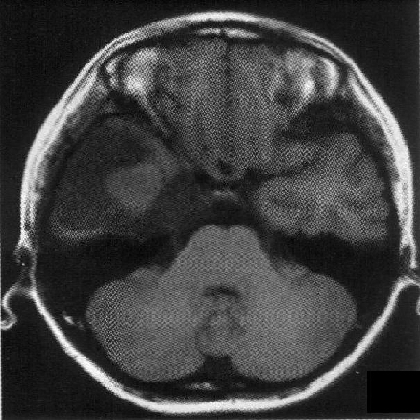

标题: PED1818:男,13岁。头痛5天,复视、呕吐3天。体检:神经生 [打印本页]

标题: PED1818:男,13岁。头痛5天,复视、呕吐3天。体检:神经生

右中颅窝见囊性占位影,其中央见块状高密度影,高密度块后后缘见条状钙化?前部与殘存颞叶皮质相连,临近骨质无异常,病灶囊变区呈长t1长t信号,实性区呈中等信号,增强(最后两副是增强t1像吧)有明显强化,实性块影上部尚见鸟嘴状影(比较像脑膜尾),考虑右中颅窝脑膜瘤可能性大,不排除室管膜瘤,畸胎瘤等

病理:囊性脑膜瘤